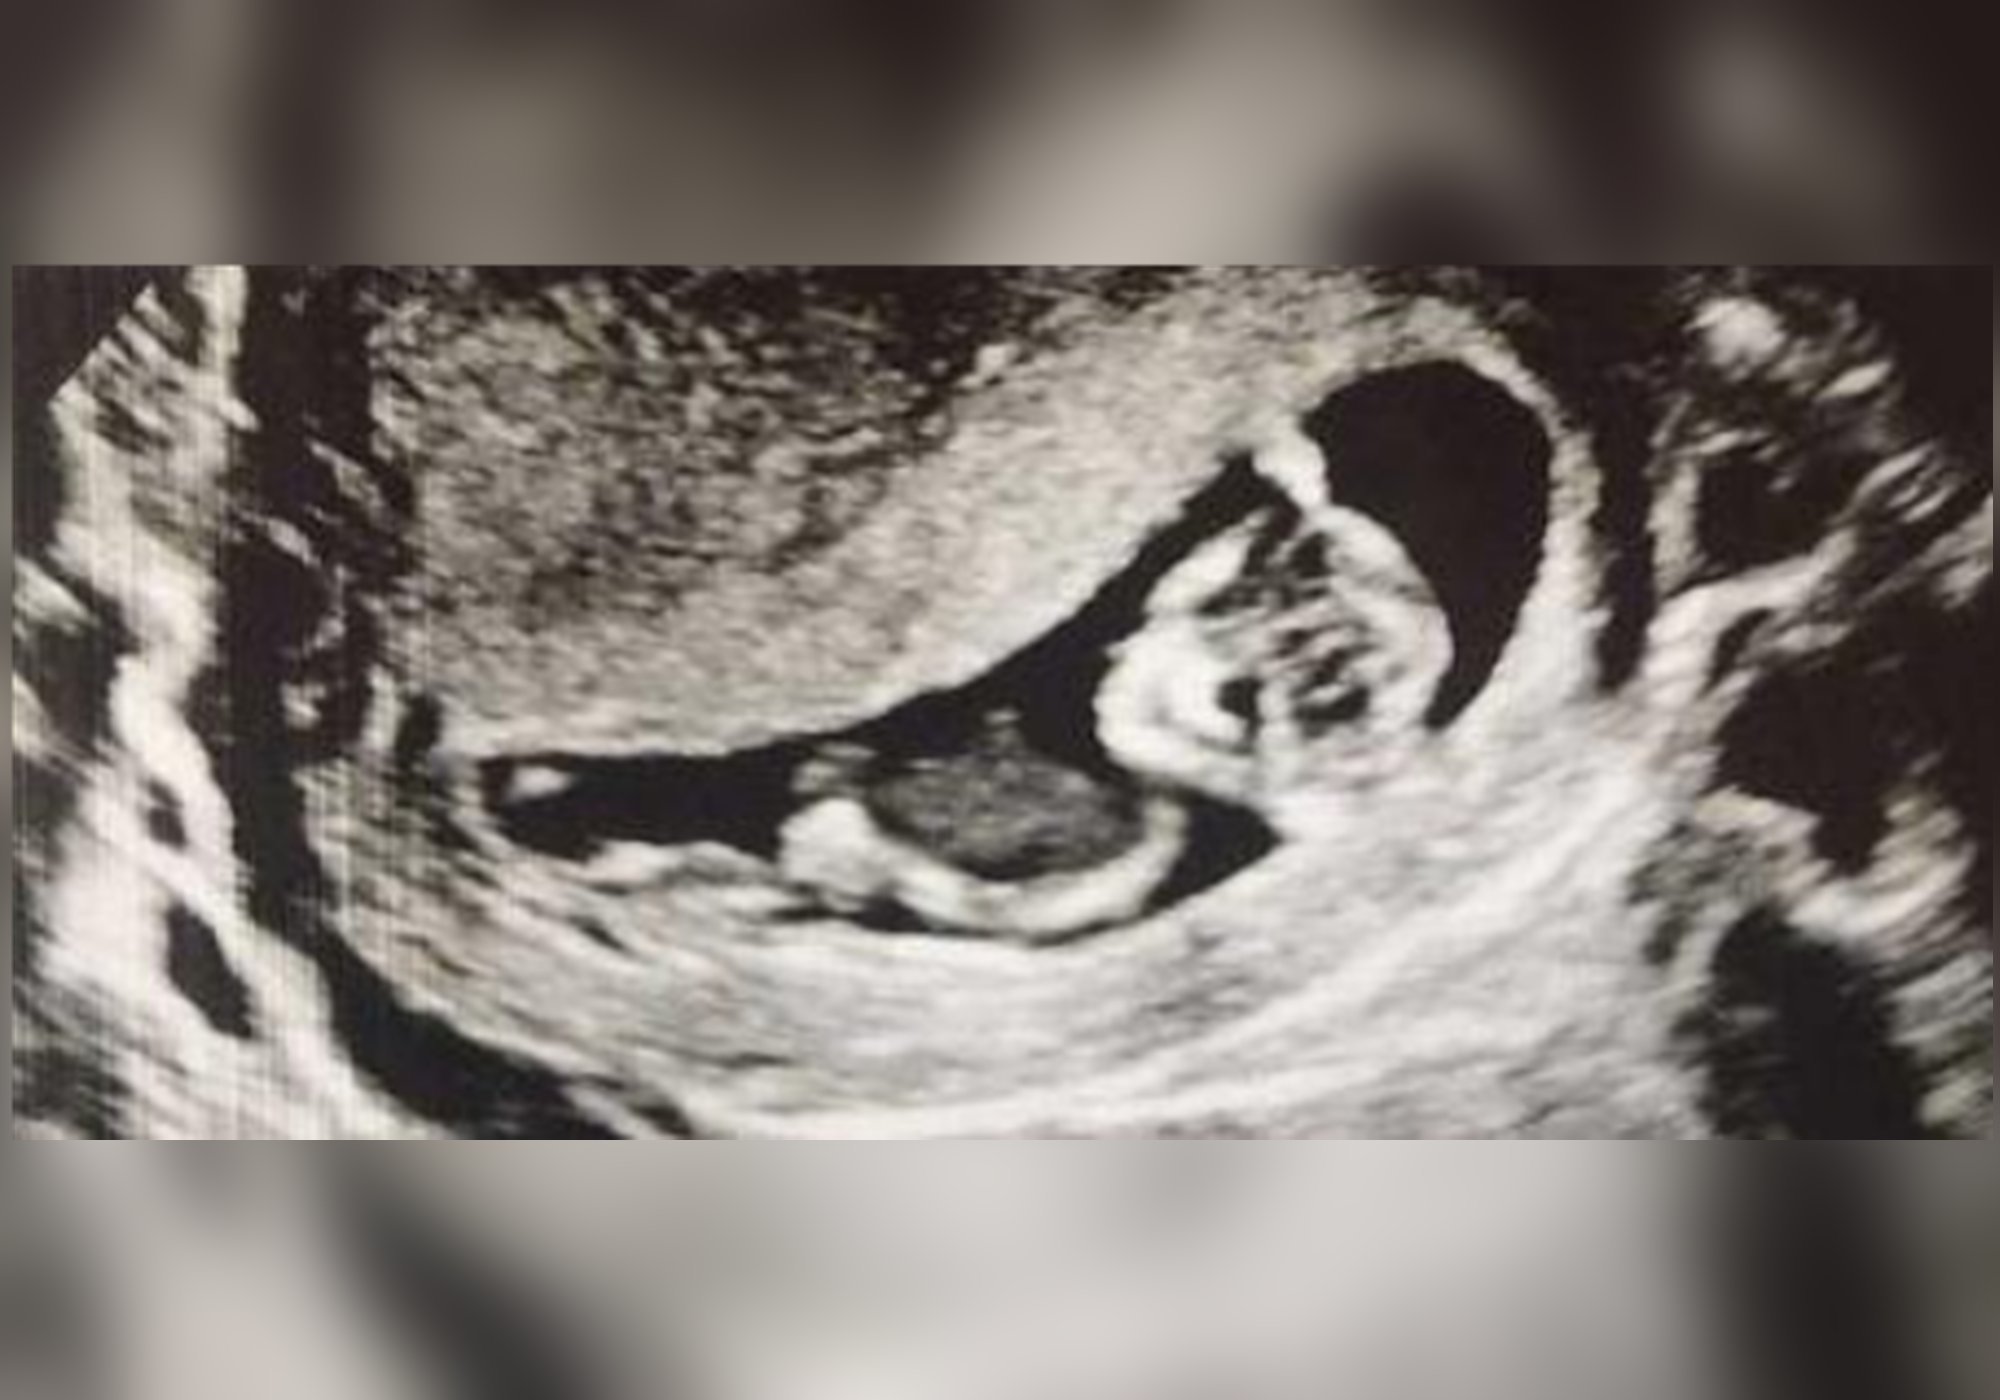

在怀孕后,准妈妈们会迫切地想要知道肚子里怀的是单胎还是多胎。但是在怀孕伊始这是不能够被判断出来的,通常在怀孕七周以后进行彩超才能够确定。

如果这时候可以看到两个胎囊在发育,这证明准妈妈们肚子中有两个小宝宝正在快速的成长。不过正常情况下,自然受孕所孕育的双胞胎从概率上讲是较少的,所以能够孕育双胞胎确实是一件非常幸运的事。当然这也意味着孕妈在孕期要经受更多的辛苦。

不过在几周以后,这位孕妈再次去参加孕检时,却被医生告知两个胎儿的发育速度有所不同,尤其是从b超上看其中一个胎儿看上去在大小上明显小了许多,并且在进行胎心监测的时候发现只能够听到一个宝宝的胎心。孕妈对此表示很难接受,于是反复地进行了检查,最终得到的结论都是一致的。

更加特别的情况是,在13周的时候孕妈再进行产检,发现腹中只能够看到一位宝宝的b超影像,那个发育较慢的胎儿居然被吸收了。为此这位孕妈心情很是低落,甚至为消失的那个宝宝取了名字留作纪念,还把当时检查的b超影像保留了下来。